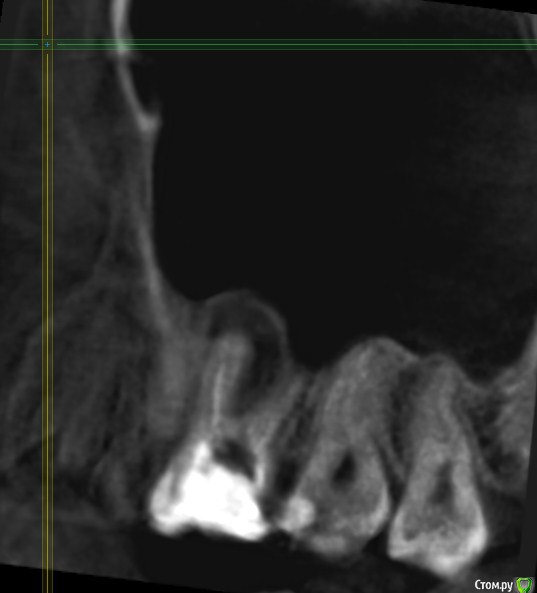

Здравствуйте! Мне показано удаление из-за кисты.

Беспокоит зуб очень редко: при жевании жесткого возникает боль, затем ноет, даже больше пульсирует, а потом еще как бы чешется внутри, где десна. Бывает, что левая ноздря-пазуха как бы "пощипывает", и как бы подзакладывает, но при этом нос дышит нормально.

Собираюсь, не откладывая до прорыва в гайморову пазуху, обратиться за лечением-решением этого моего вопроса со здоровьем.

Подскажите, пожалуйста, точно удалять? Как принять это решение, все таки надежда на какой то другой лечебный вариант теплится =)post-59509-0-08196600-1578493080_thumb.jpgpost-59509-0-63211400-1578493088_thumb.jpgpost-59509-0-77705800-1578493096_thumb.jpgpost-59509-0-02698500-1578493106_thumb.jpgpost-59509-0-04880900-1578493120_thumb.jpgpost-59509-0-11411000-1578493128_thumb.jpg

Найдите терапевта, занимающегося эндодонтическим лечением зубов с использованием микроскопа. Окончательный вердикт все равно можно выдать только взглянув через увеличение в сам зуб.

По представленным срезам создаётся впечатление, что лечение вполне возможно